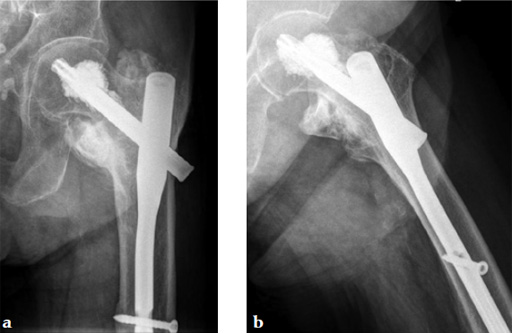

An 82-year-old woman with an unstable pertrochanteric fracture of the right proximal femur. Her Barthel Index was 80 and her preoperative Parker mobility score was 5, which means that she was walking at home unassisted. The patient's preoperative Parker mobility score of 5 was reached again at the 3-month follow-up.

Augmentation of a proximal femoral nail construct